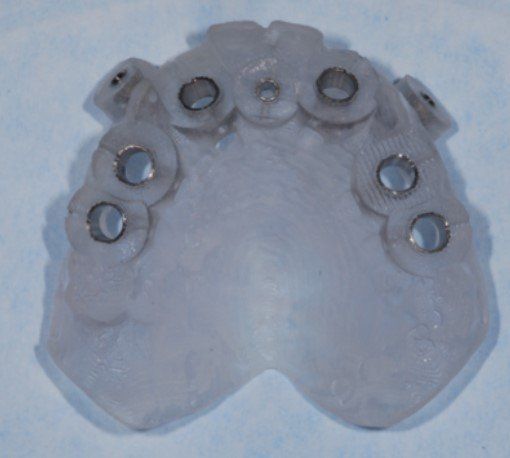

Una volta raccolti i dati clinici del paziente, utili per la compilazione della cartella clinica, le immagini radiologiche (TAC) che richiediamo per la pianificazione vengono acquisite ed elaborati con un software computerizzato specifico per l'implantologia dentale. Tale programma consente di evidenziare tridimensionalmente i mascellari del paziente e di eseguire una pianificazione con l’inserimento virtuale degli impianti, in modo tale da avere una previsione molto precisa del risultato finale. A pianificazione ultimata il file viene inviato via internet a un'azienda belga, che con una tecnica computerizzata produce una guida chirurgica, che utilizzeremo in sede di intervento.

Gli impianti dentro l’osso vengono inseriti attraverso piccoli fori realizzati nella gengiva in anestesia locale, senza utilizzare il bisturi tradizionale.